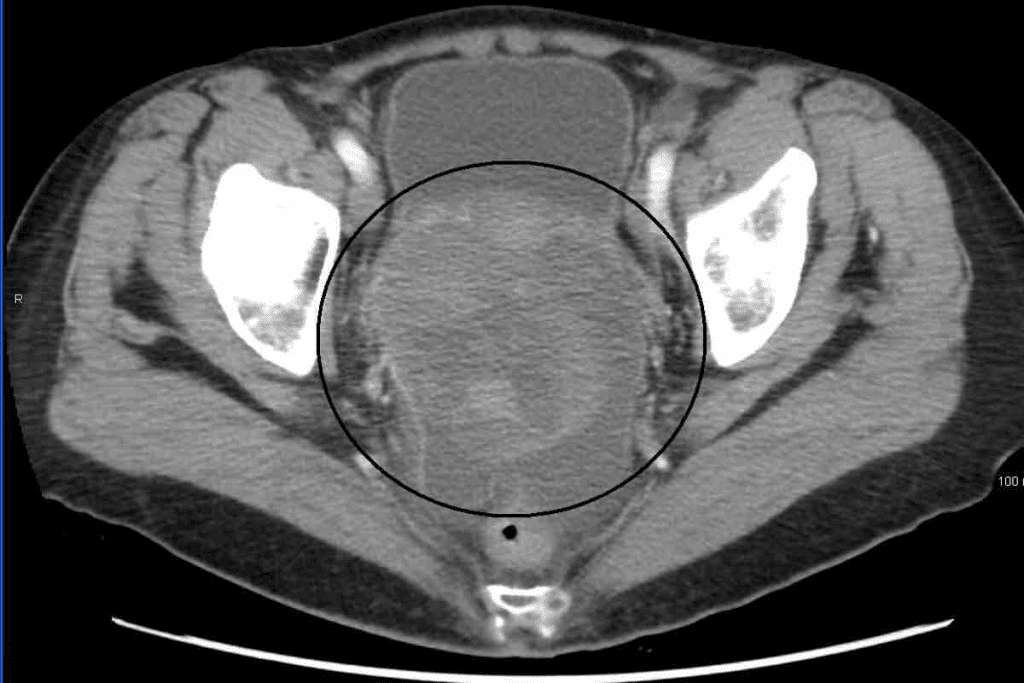

Normal Uterine Appearance on CT Imaging

The normal uterus shows clear signs on CT scans. These signs help doctors spot any problems. It’s important to know what a normal uterus looks like on a CT scan.

Homogeneous Enhancement Patterns After Contrast

A normal uterus shows a homogeneous enhancement pattern after contrast. This means the uterus gets contrast evenly. This evenness shows the uterus is healthy and working properly.

Zonal Anatomy Visualization

A normal uterus also shows clear zonal anatomy on CT scans. The uterus has layers like the endometrium, myometrium, and serosa. These layers are visible after contrast, helping doctors check their thickness and health.

Identifying Abnormal CT Scan of Neck with Contrast: Uterine Findings

Contrast CT scans of the neck can show unexpected uterine issues. It’s key to spot both normal and abnormal uterine findings. This helps in giving accurate diagnoses and care.

Uterine Masses and Their Distinguishing Features

Uterine masses on CT scans can differ in size and importance. Leiomyomas (fibroids) are benign tumors seen as defined masses in the uterine wall.

Features of uterine masses on CT scans include:

- Size and location: Size and location can affect their clinical meaning.

- Enhancement patterns: How a mass changes after contrast can hint at its type.

- Margins and borders: Clear margins often mean benign, while irregular ones might suggest cancer.